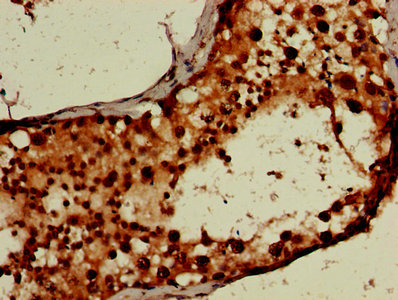

CSB-PA897459LA01HU

IHC image of CSB-PA897459LA01HU diluted at 1:600 and staining in paraffin-embedded human testis tissue performed on a Leica BondTM system. After dewaxing and hydration, antigen retrieval was mediated by high pressure in a citrate buffer (pH 6.0). Section was blocked with 10% normal goat serum 30min at RT. Then primary antibody (1% BSA) was incubated at 4°C overnight. The primary is detected by a biotinylated secondary antibody and visualized using an HRP conjugated SP system.